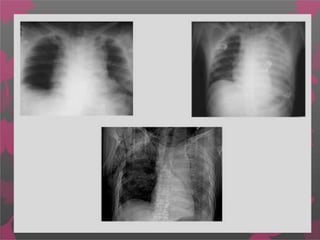

Signos radiológicos de una lesión vascular grave :

 Ensanchamiento del mediastino

 Obliteración del botón aórtico

 Desviación de la tráquea hacia la derecha

 Depresión del bronquio principal izquierdo

 Elevación del bronquio principal derecho

 Obliteración del espacio entre la arteria pulmonar y la aorta

(oscurecimiento de la ventana aortopulmonar)

 Desviación del esófago (sonda nasogástrica) hacia la derecha

 Ensanchamiento de la línea paratraqueal

 Ensanchamiento de la interfase paravertebral

 Presencia de una sombra pleural apical

 Hemotórax izquierdo

 Fracturas de la primera o segunda costilla, o de la escápula